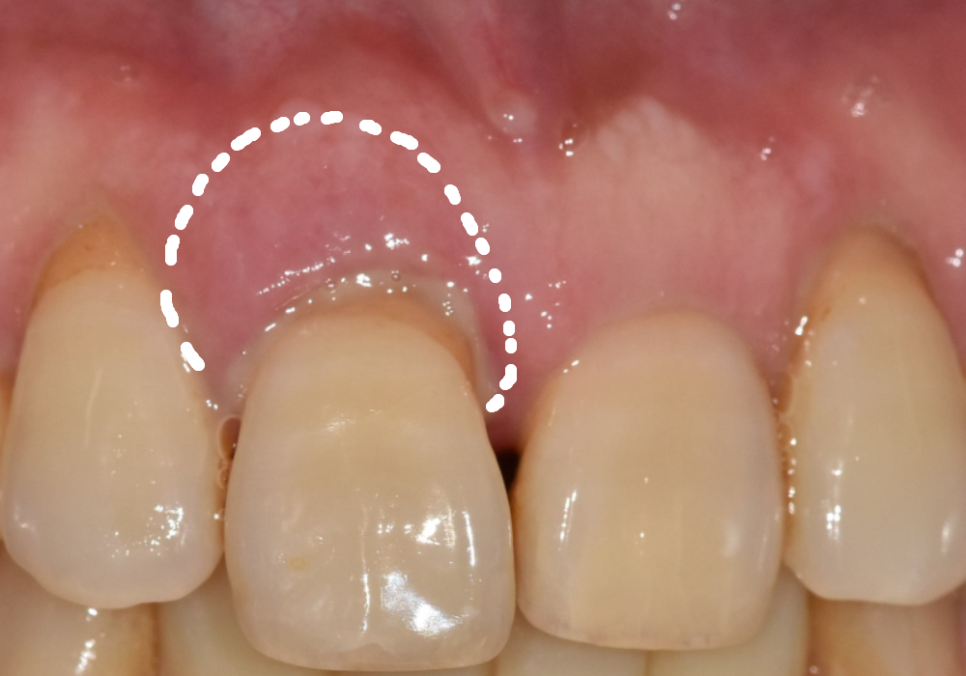

입안을 살펴보니 위 가운데 앞니(#11)가

옆 치아들에 비해 확연히 아래로 내려와 있었어요.

그러다 보니 치아가 삐뚤어 보이는

느낌이 드는데요~

외관상 보기 좋지 않은 것도 문제지만,

사실 그보다 더 큰 본질적인 문제는

'잇몸'에 있었습니다.

잇몸 주위가 빨갛게 부어 있었고,

살짝만 눌러도 고름이 맺힐 정도로

염증이 심한 상태....